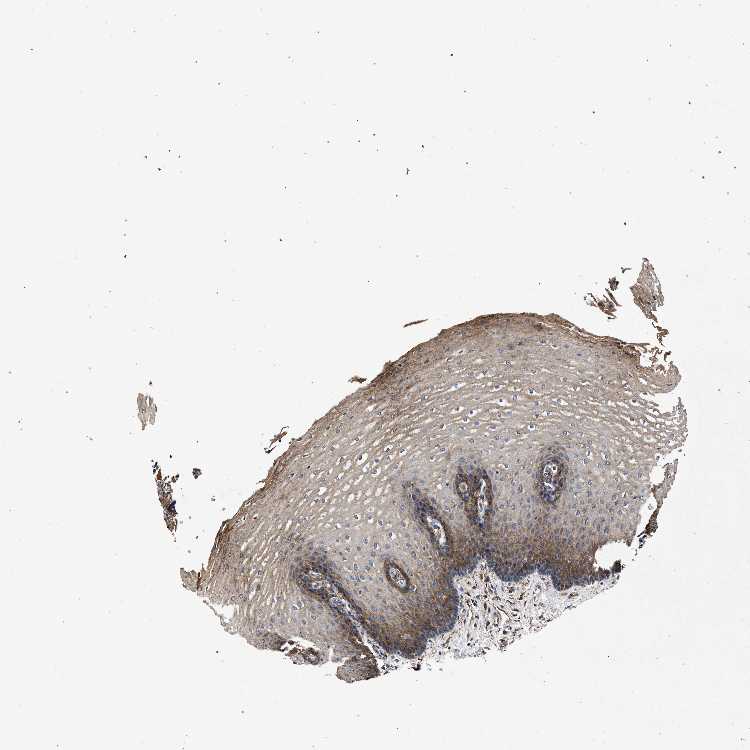

ESOPHAGUS - Antibody stainingi

Antibody staining in the annotated cell types in the current human tissue is reported as not detected, low, medium, or high, based on conventional immunohistochemistry profiling in selected tissues. This score is based on the combination of the staining intensity and fraction of stained cells.

Each image is clickable and will lead to virtual microscopy that enables deeper exploration of all samples and also displays staining intensity scores, fraction scores and subcellular localization as well as patient and tissue information for each sample.

Antibody HPA067595Antibody HPA069443Antibody CAB022062

Squamous epithelial cells MediumLowMedium